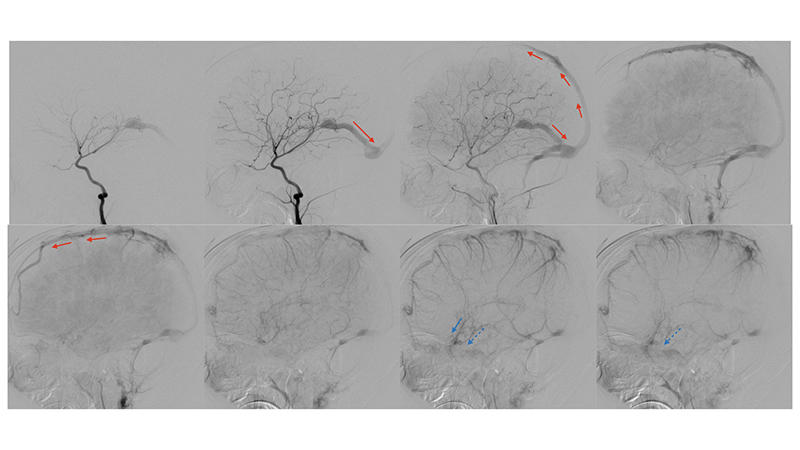

- Πλαγία λήψη κατά την έγχυση στην αριστερή σπονδυλική αρτηρία. Τροφοφόροι θαλαμοδιατιτραίνοντες (διακεκομμένο μαύρο βέλος) και υποεπενδυματικοί κλάδοι (διακεκομμένο μπλέ βέλος), εκ της οπισθίας αναστομωτικής και του Ρ1 τμήματος των οπισθίων εγκεφαλικών αρτηριών, που πορευόμενοι στο πλάγιο τοίχωμα της 3ης κοιλίας εκατέρωθεν, συναντούν την χοριοειδή σχισμή και εκείθεν αρδεύουν την αρτηριοφλεβώδη επικοινωνία (μαύρα βέλη). Παρατηρείται αναστροφή της ροής στον άνω οβελιαίο κόλπο με φλοιώδη παλινδρόμηση προς τα εγκεφαλικά ημισφαίρια αμφοτερόπλευρα (κόκκινα βέλη). Οι εγκάρσιοι κόλποι αποφράσσονται, και μέσω των περιμεσεγκεφαλικών φλεβών παρατηρείται παροχέτευση προς το περιμυελικό φλεβικό δίκτυο του νωτιαίου μυελού (μπλέ βέλη) το οποίο παρουσιάζει εκσεσημασμένη συμφόρηση αλλά και διά του άνω λιθοειδούς κόλπου προς τον σηραγγώδη κόλπο (μαύρα βέλη).

Το παιδί μετά τον πρώτο εμβολισμό παρουσίασε άμεση κλινική βελτίωση, με πλήρη αποκατάσταση της κινητικότητος του. - Προσθιοπίσθια λήψη κατά την έγχυση στην αριστερή έσω καρωτίδα ένα μήνα μετά την επέμβαση. Παρατηρείται θρόμβωση του ευθέως κόλπου και της περιοχής του Ληνού του Ηροφίλου καθώς και του τελικού τμήματος του άνω οβελιαίου κόλπου και των εγκαρσίων κόλπων. Ο μηχανισμός της θρομβώσεως, αποδίδεται στην σημαντική ελάττωση της ροής μέσα στο φλεβικό αποχετευτικό δίκτυο της φλέβας του Γαληνού και του ευθέως κόλπου που πιθανότατα οδήγησε σε φλεβική στάση και θρόμβωση.

- Πλαγία λήψη κατά την έγχυση στην αριστερή έσω καρωτίδα ένα μήνα μετά την επέμβαση. Παρατηρείται ελάχιστη άρδευση της επικοινωνίας από οπίσθιους χοριοειδείς κλάδους των οπισθίων εγκεφαλικών, καθώς και από θαλαμοδιατιτραίνοντες κλάδους που εκφύεται από το Ρ1 της αριστερής οπισθίας εγκεφαλικής αρτηρίας. Η φλεβική παροχέτευση της επικοινωνίας γίνεται προς την φλέβα του Γαληνού που είναι σημαντικά λιγότερο διατεταμένη, και δια μέσου επιπολής φλεβός της έσω επιφανείας του αριστερού βρεγματικού φλοιού προς τον αποσυμφορημένο πιά άνω οβελιαίο κόλπο. Η φλεβική αποχέτευση του ημισφαιρίου γίνεται προς το σύστημα του αριστερού σηραγγώδους κόλπου, με σημαντική αιμοδυναμική αποσυμφόρηση των ημισφαιρικών φλεβών που πλέον σκιαγραφούνται σε φυσιολογικό χρόνο.

- Προσθιοπίσθια λήψη κατά την έγχυση στην αριστερή σπονδυλική αρτηρία. Επανελέγχεται ελάχιστη υπολειμματική άρδευση της επικοινωνίας από οπίσθιους χοριοειδείς κλάδους των οπισθίων εγκεφαλικών, καθώς και από θαλαμοδιατιτραίνοντες κλάδους που εκφύεται από το Ρ1 της αριστερής οπισθίας εγκεφαλικής αρτηρίας, με θρόμβωση του ευθέως κόλπου και της περιοχής του Ληνού του Ηροφίλου καθώς και του τελικού τμήματος του άνω οβελιαίου κόλπου και των εγκαρσίων κόλπων.

- Πλαγία λήψη κατά την έγχυση στην αριστερή σπονδυλική αρτηρία. Η φλεβική παροχέτευση γίνεται προς την φλέβα του Γαληνού, και διά μέσου επιπολής φλεβός προς την έσω επιφάνεια του αριστερού βρεγματικού λοβού προς τον άνω οβελιαίο κόλπο, κατά την μετάπτωση του μέσου προς οπίσθιο τριτημόριο. Επίσης μέσω υποεπενδυματικών φλεβών που πορεύονται ενδοκοιλιακά αμφοτερόπλευρα και εκβάλλουν διά των άνω λιθοειδικών φλεβών προς το τους εγκαρσίους κόλπους, με πορεία προς τοην περιοχή του Ληνού που φαίνεται να έχει επανασηραγγοποιηθεί. Παρατηρείται αποσυμφόρηση του περιμεσεγκεφαλικού φλεβικού δικτύου με σημαντική ελάττωση της φλεβικής συμφορήσεως περιμεσεγκεφαλικά καθώς και προς τον νωτιαίο μυελό.